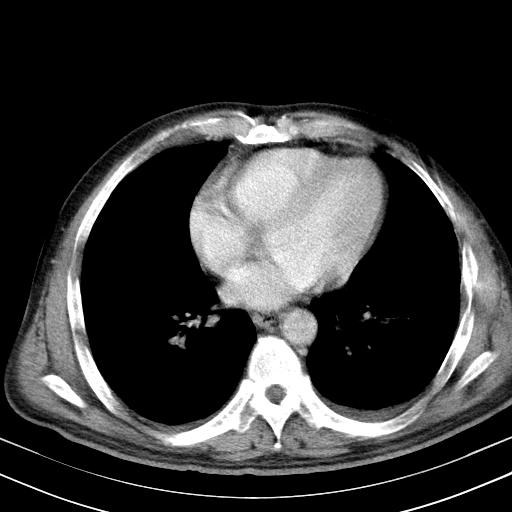

先行ct平扫,纵膈内多发软组织影,ct值约为36hu,以下为增强扫描和腹部平扫。

请会诊

经典?纵膈多发肿大淋巴结。腹膜后未见异常。

1)考虑淋巴瘤。2)双侧少量胸腔积液。